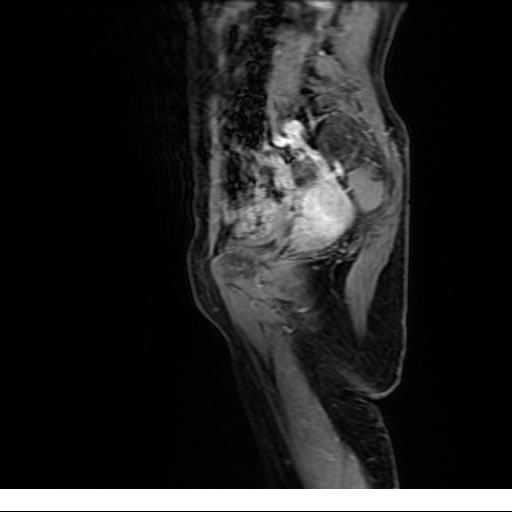

Se realizan adquisiciones en diferentes planos, con secuencias Spin echo y GRE, ponderadas a T1 y a T2, se utilizan pulsos de saturación de grasa y se administra medio de contraste a base de gadolinio.

El útero está en retroversión, retroflexión, y en posición central, se observa liquido en la cavidad endometrial, debido a la presencia de un Ca endometrial; en el anexo derecho se observa una masa quística que mide 3.8 x 2.2 cm de diámetro, corresponde a un quiste bilobulado, posee pared gruesa con componente solido puede tratarse de un Cistoadenocarcinoma, el cual realza con el medio de contraste de forma importante, entra dentro de una clasificación O-Rad tipo IV compatible con un Cistoadenocarcinoma

O-RAD tipo IV, Cistoadenocarcinoma